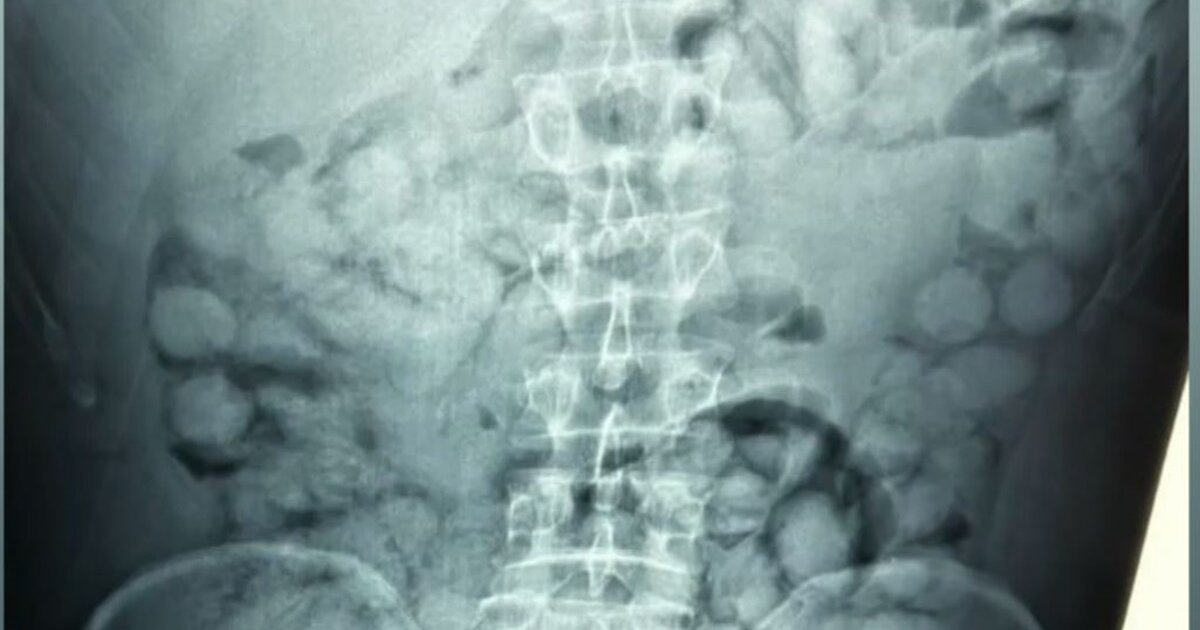

Στις ακτινογραφίες που έδωσε στη δημοσιότητα η Ελληνική Αστυνομία, διακρίνονται οι συσκευασίες που είχε καταπιεί με τους γιατρούς να εντοπίζουν 100 κάψουλες των 11 γραμμαρίων η καθεμία.

Η συγκεκριμένη μέθοδος διακίνησης ναρκωτικών είναι εξαιρετικά επικίνδυνη, αφού αν άνοιγε στο στομάχι του έστω και μία συσκευασία, σε λίγα λεπτά θα είχε πεθάνει. Σύμφωνα με τις πρώτες πληροφορίες, η συνολική ποσότητα κοκαΐνης που εντοπίστηκε ξεπερνάει το ένα κιλό. Η έρευνα των αρχών συνεχίζεται για τον εντοπισμό και άλλων εμπλεκομένων στην υπόθεση.